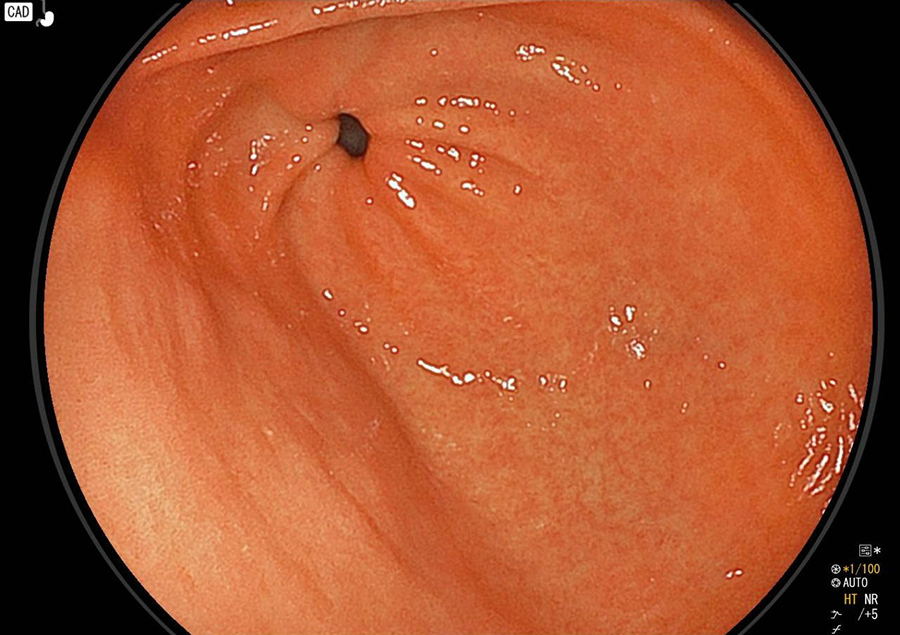

白色粘液付着

炎症によって白い粘液が付着し、胃のひだがむくんで腫れています。